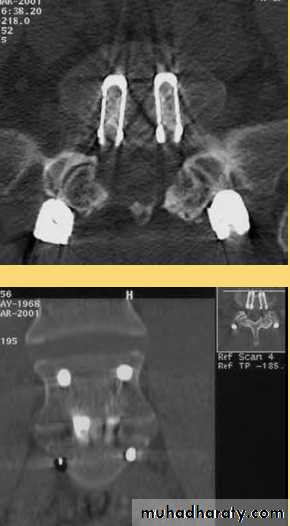

Computed Tomography

The current role of CT is for patients with contraindications for MRI (e.g. pacemaker). In the latter case, CT is often combined with myelography (myelo-CT) to provide conclusions on potential neural compression.in the evaluation of patients postoperatively to assess lumbar fusion status.